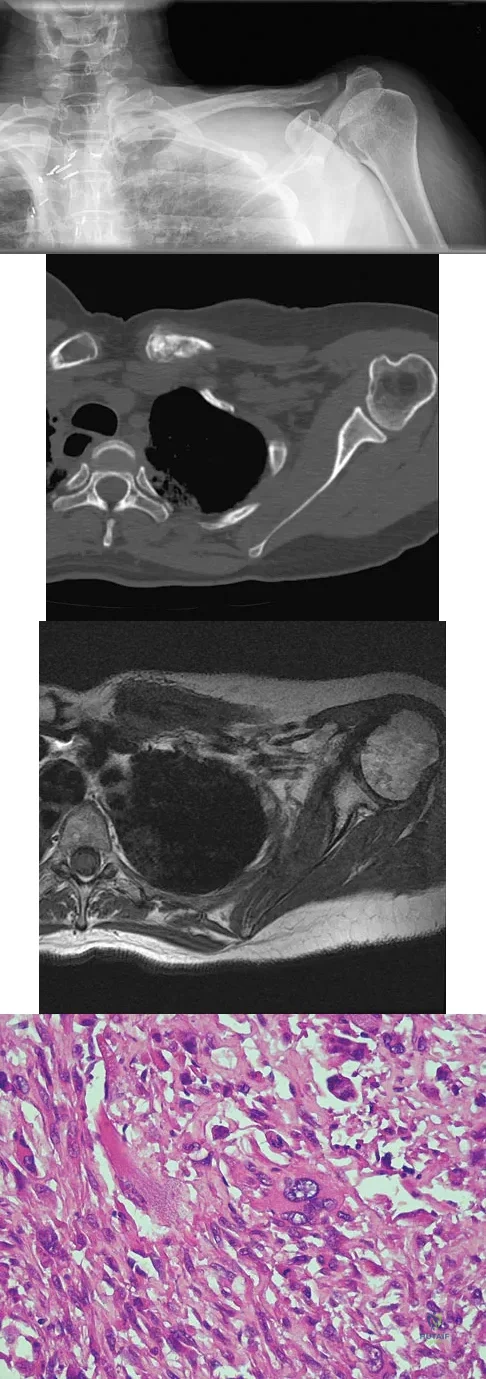

Question 27

A 47-year-old woman has had left medial clavicle pain for the past 6 months. History is remarkable for mediastinal non-Hodgkin's lymphoma, treated with mantel radiation 22 years ago. A radiograph, CT scan, MRI scan, and a biopsy specimen are shown in Figures 68a through 68d. What is the most likely diagnosis?

Explanation

A healthy 16-year-old boy has had increasing pain in the right knee for the past 3 months. Examination reveals warmth and swelling around the distal femur. Radiographs and an MRI scan are shown in Figures 51a through 51c, and a biopsy specimen is shown in Figure 51d. What is the most likely diagnosis?

Explanation